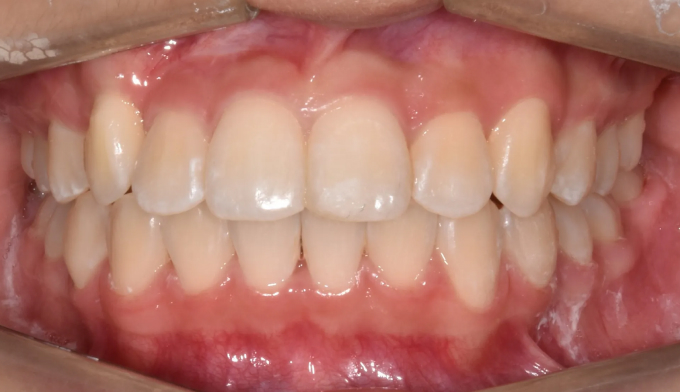

한쪽에는 덧니, 다른 한쪽에는 매복치가 있는 케이스입니다.

총 치료기간은 17개월 소요되었습니다.